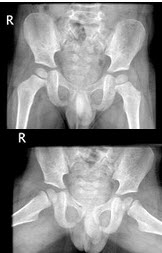

26、单项选择题

男,根据其正常盆腔影像图像,判断其最可能的年龄()

A.15岁左右

B.12岁左右

C.6岁左右

D.3岁左右

E.9岁左右